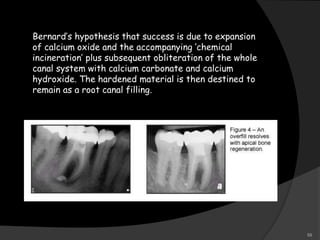

Bernard’s hypothesis that success is due to expansion

of calcium oxide and the accompanying ‘chemical

incineration’ plus subsequent obliteration of the whole

canal system with calcium carbonate and calcium

hydroxide. The hardened material is then destined to

remain as a root canal filling.